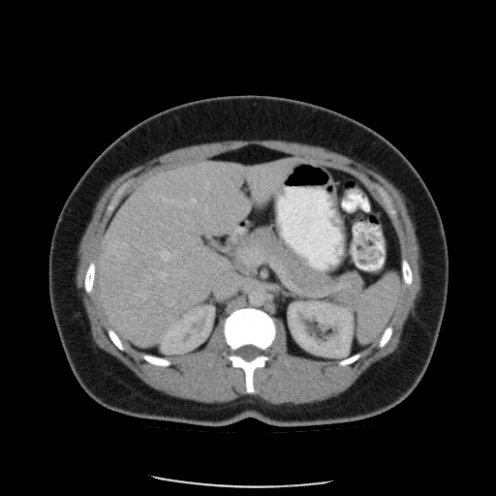

Paciente de 66 años con antecedente de pancreatitis, tomografía control.